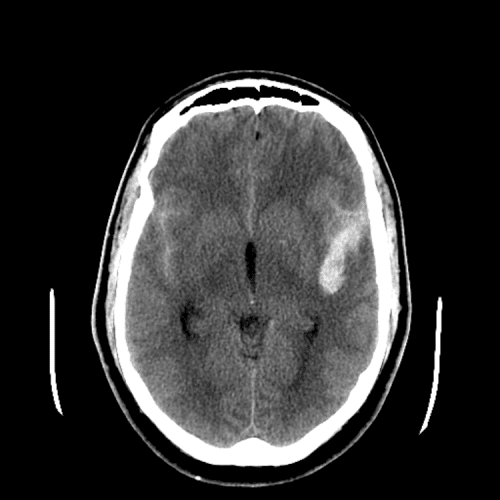

ACA and MCA territory infarct